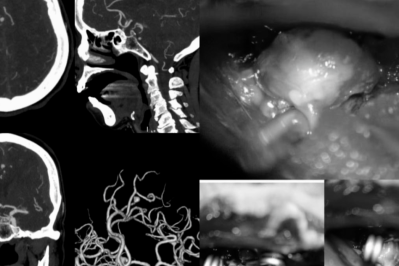

桂林医科大学第二附属医院(第二临床医学院)是桂林医科大学直属的现代化大型综合医院,邻近桂林市政府和桂林医科大学新校区(主校区),交通便利,环境优雅。医院始建于1942年,2014年更名为桂林医学院第二附属医院,2025年更名为桂林医科大学第二附属医院,占地面积82900平方米,编制床位数1200张,是一家集医疗、教学、科研、预防、康复、急救为一体的国家三级甲等综合医院,为全国百姓放心示范医院、自治区文明单位、国家药物临床试验机构、自治区首批药品临床综合评价基地。 学科齐全,锻造办院特色。医院设有53个临床、医技科室,86个专科、专病门诊,16个护理门诊,并在广西率先建立了独立的脑血管病(脑卒中)诊疗专科,桂林市首家家庭式产待一体化产房,切实提供优质高效的诊疗服务。 实力强劲,推动内涵提升。医院现有13个广西医疗卫生重点(培育)学科(呼吸与危重症医学科、感染性疾病科、心血管内科、儿科、麻醉科、重症医学科、急诊医学科、普通外科、骨科、产科、肿瘤内科、神经内科、消化内科),3个广西临床重点专科建设(培育)项目(心血管内科、风湿免疫科、泌尿外科),5个市级重点专科(麻醉科、临床药学、心血管内科、肿瘤科、肝病科(传染病方向)),是国家高级卒中中心、中国胸痛中心、中国房颤中心、全国乳腺癌规范诊疗示范中心建设单位、首批国家级神经介入建设中心、国家标准化过敏性疾病诊疗中心、广西产前诊断机构、桂林市超声诊断质量控制中心、桂林市危重孕产妇救治中心和危重新生儿救治中心、桂北地区唯一一家毒蛇咬伤救治中心。一流的专科,卓越的实力,为广大百姓健康保驾护航。近年来,医院门急诊人次、出院病人数和手术台次稳步提升,诊疗范围辐射桂北地区及邻近省市,服务人口近2000万。 创新驱动,科研平台优越。医院大力实施科教兴院战略,坚持用科研创新推动医院发展,现有国家级研究平台——国家代谢性疾病临床医学研究中心分中心,省级临床研究平台——广西糖尿病及代谢疾病临床医学研究中心,省级重点实验室——广西慢性病代谢重塑与智能医学工程重点实验室,厅级研究平台——广西糖脂代谢病重点实验室、广西高校呼吸疾病重点实验室,广西高校高水平创新团队——慢性肺部高发性疾病研究团队,以及广西博士后创新实践基地等多个科研平台。